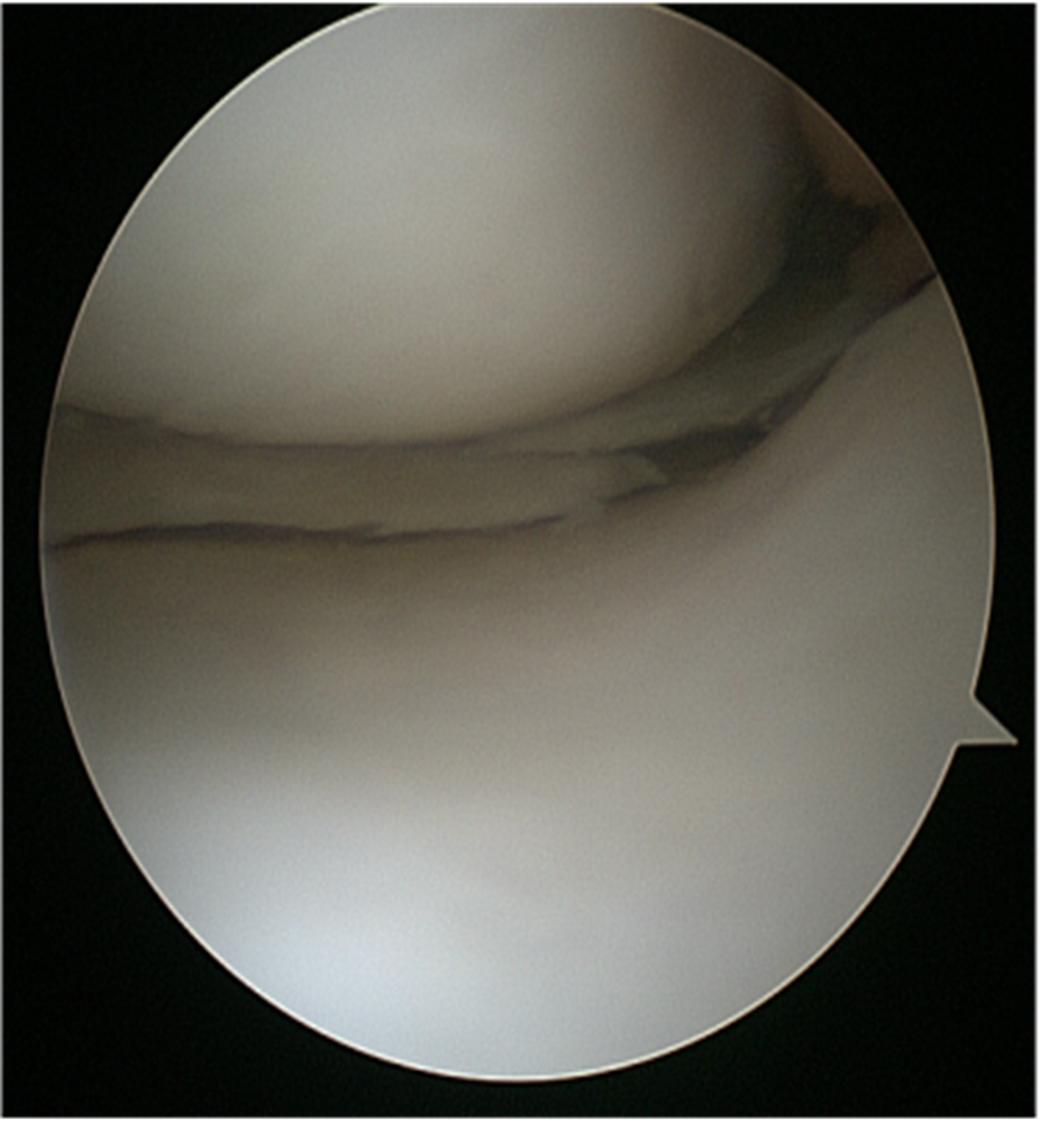

Orthopaedic surgeons perform arthroscopic surgery by making a small incision in the patient’s skin and inserting pencil-size instruments that contain a small lens and lighting system to magnify and illuminate the structures inside the joint. A fibre optic cable transmits light to the end of the arthroscope inserted into the joint. An arthroscope is attached to a miniature camera so the surgeon can see inside the joint through this small incision rather than a larger one required for open surgery.

A small incision (about the size of a buttonhole) will be made to insert the arthroscope. Several other incisions may be made to see other parts of the joint or insert other instruments.

Corrective surgery is performed with specially designed instruments that are inserted into the joint through accessory incisions. Originally, arthroscopy was simply a diagnostic tool used for planning standard open surgery.